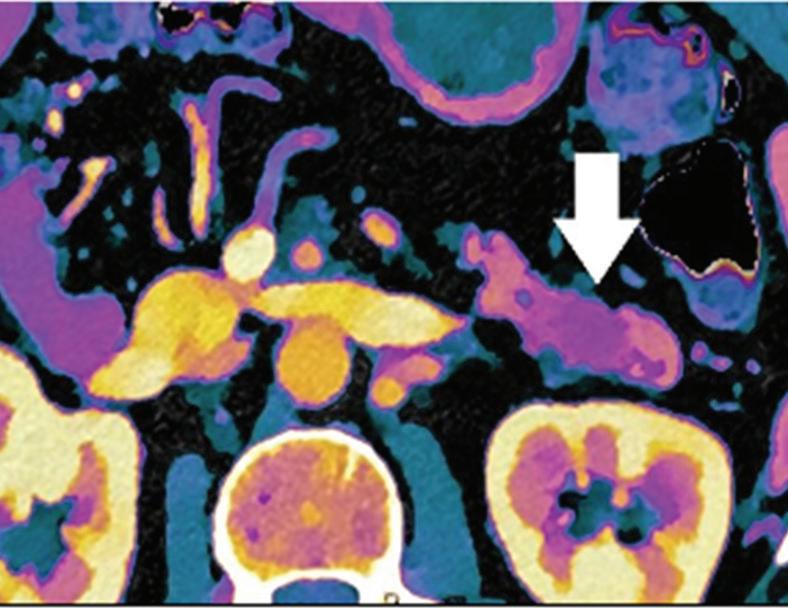

A small isoattenuating pancreatic adenocarcinoma (arrow), (a) which tend to blend into normal parenchyma on conventional axial CT image, acquired at pancreatic parenchymal phase with administration of 70 ml of contrast material (iodine concentration 350 mg/ml). (b) Monoenergetic 50 keV and (c) Z effective images improve detection by increasing conspicuity and contrast between tumor and normal parenchyma.

Pancreatic tumors. Several studies have demonstrated an obvious advantage of DECT for detection and staging of pancreatic adenocarcinoma using the low-monoenergetic data sets (Figure 5), regardless of the timing of the acquisition applied (single venous phase,55 pancreatic parenchymal phase,56 single split bolus single acquisition57).